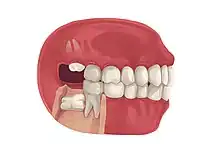

Impacted wisdom teeth is a condition where the third molars (wisdom teeth) are prevented from erupting into the mouth.[1] This can be caused by a physical barrier, such as other teeth, or when the tooth is angled away from a vertical position.[2] Completely unerupted wisdom teeth usually result in no symptoms, although they can sometimes develop cysts or neoplasms. Partially erupted wisdom teeth or wisdom teeth that are not erupted but are exposed to oral bacteria through deep periodontal pocket, can develop cavities or pericoronitis. Removal of impacted wisdom teeth is advised for the future prevention of or in the current presence of certain pathologies, such as caries (dental decay), periodontal disease or cysts. Prophylactic (preventative) extraction of wisdom teeth is preferred to be done at a younger age (middle to late teenage years) to take advantage of incomplete root development, which is associated with an easier surgical procedure and less probability of complications.[3]

Impacted wisdom teeth are often described by the direction of their impaction (forward tilting, or mesioangular being the most common), the depth of impaction and the age of the patient as well as other factors such as pre-existing infection or the presence of pathology (cysts, tumors or other disease).[5]: 143–144 Each of these factors is used to predict the difficulty (and rate of complications) when removing an impacted tooth, with age being the most reliable predictor[8] rather than the orientation of the impaction.[9]